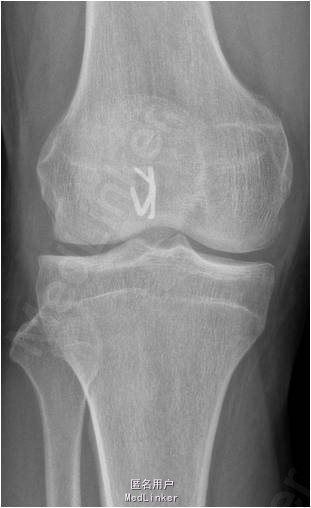

患者男,41岁,因“右膝关节镜术后3月余,依约返院”入院。患者3个月前因右膝髌股关节剥脱性骨软骨炎行“右膝关节门型钉固定术”,现患者依约返院行“门型钉取出术”。

诊断:1.右膝髌股关节剥脱性骨软骨炎术后;2.右膝关节半月板修补术后 行右膝关节镜检及门型钉取出术。术后第二天右膝关节可以开始负重。